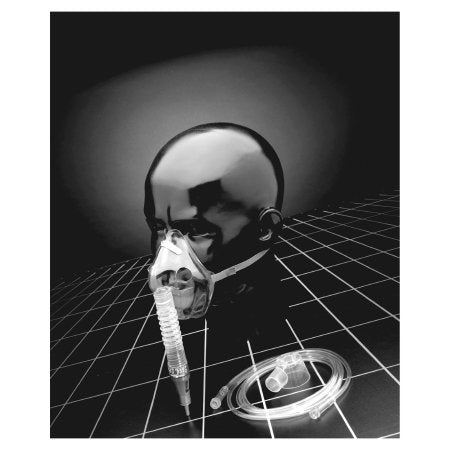

Air Entrainment Mask Percent-O2-Lock Elongated Style Adult One Size Fits Most Adjustable Head Strap

The Percent-O2-Lock Air Entrainment Mask by Sun Med provides precise and adjustable oxygen delivery, making it ideal for both short- and long-term respiratory therapy. Featuring a variable Venturi system, it offers controlled oxygen concentrations ranging from 24% to 50%, ensuring accurate treatment across various patient needs.

Crafted from soft, clear PVC, this elongated style mask includes a trumpet connector, 7-foot oxygen tubing, and an adjustable head strap for maximum comfort and secure placement. Its design makes it especially suitable for edentulous patients or long-term oxygen users.